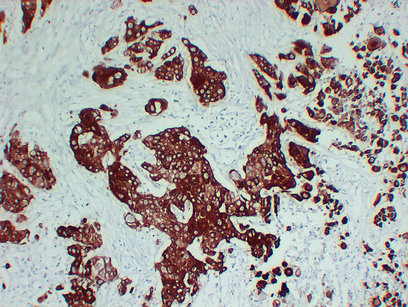

Immunohistochemistry analysis of paraffin-embedded Lung squamous cell carcinoma using Cytokeratin 6A antibody.High-pressure and temperature Sodium Citrate pH 6.0 was used for antigen retrieval.